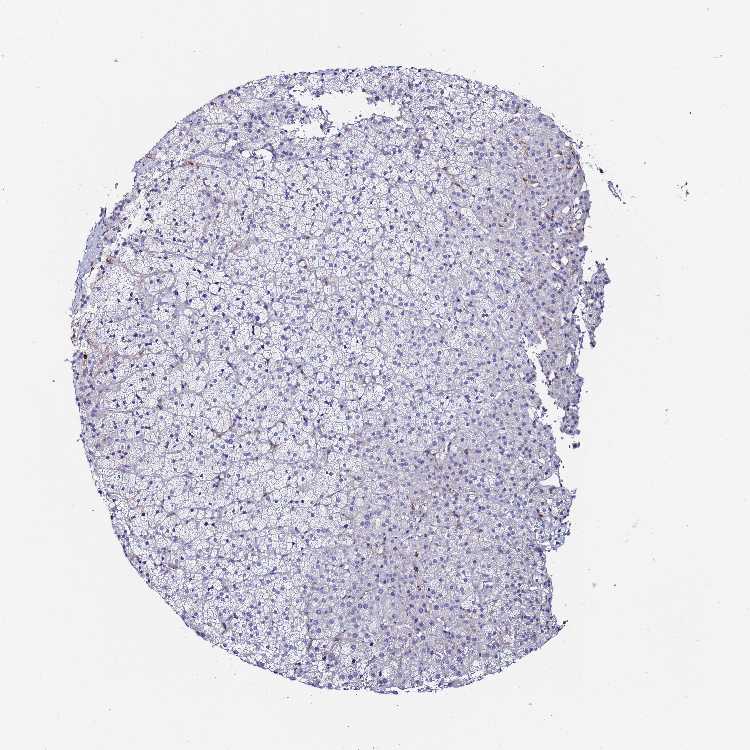

ADRENAL GLAND - Antibody stainingi

Antibody staining in the annotated cell types in the current human tissue is reported as not detected, low, medium, or high, based on conventional immunohistochemistry profiling in selected tissues. This score is based on the combination of the staining intensity and fraction of stained cells.

Each image is clickable and will lead to virtual microscopy that enables deeper exploration of all samples and also displays staining intensity scores, fraction scores and subcellular localization as well as patient and tissue information for each sample.

Antibody HPA045218Antibody HPA050333

Glandular cells Not detectedNot detected